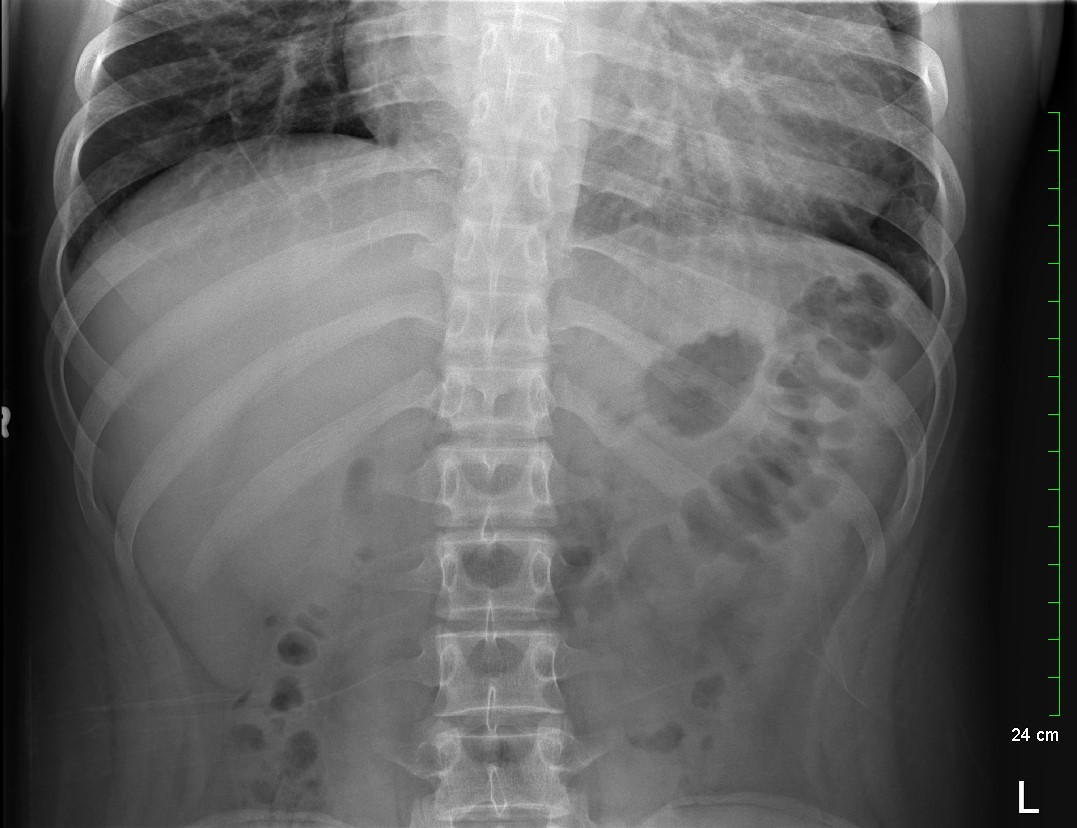

Because the patient presented with prolonged vomiting, a complete blood count (CBC), comprehensive metabolic panel (CMP), lipase, and kidney, ureter and bladder (KUB) was obtained. Initial labs showed only mild transaminitis and metabolic acidosis (AST 106, ALT 188, HCO3 15). KUB revealed the following images:

KUB read as normal by radiology. However, because of the enlarged heart border found incidentally on KUB, troponin I (0.05 ng/mL), B-type natriuretic peptide (BNP) (2186 pg/mL), and chest x-ray (CXR) was obtained, which showed the following: